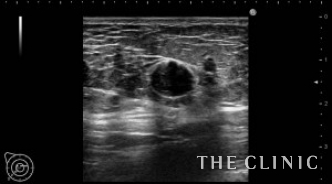

No.31でご紹介した方のオイルシストです。

右に13個・左に8個あり、それぞれ3㎜~15㎜の大きさです。

エコー下にて、穿刺吸引を行います。

全てのしこりを除去できました。